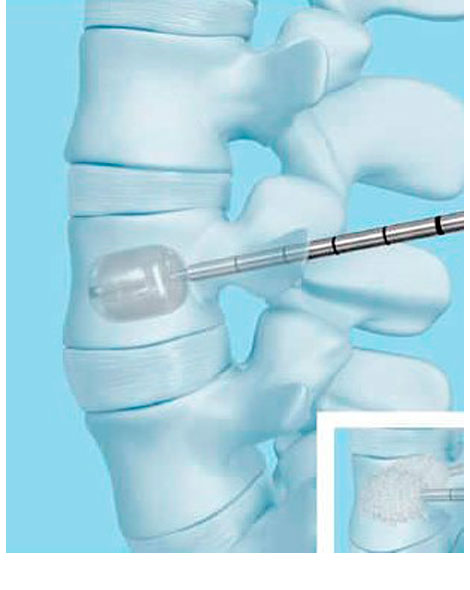

CIFOPLASTIA:

Con la cifoplastia, las fugas de cemento son menores y el stent consigue crear un armazón dentro de la vértebra.